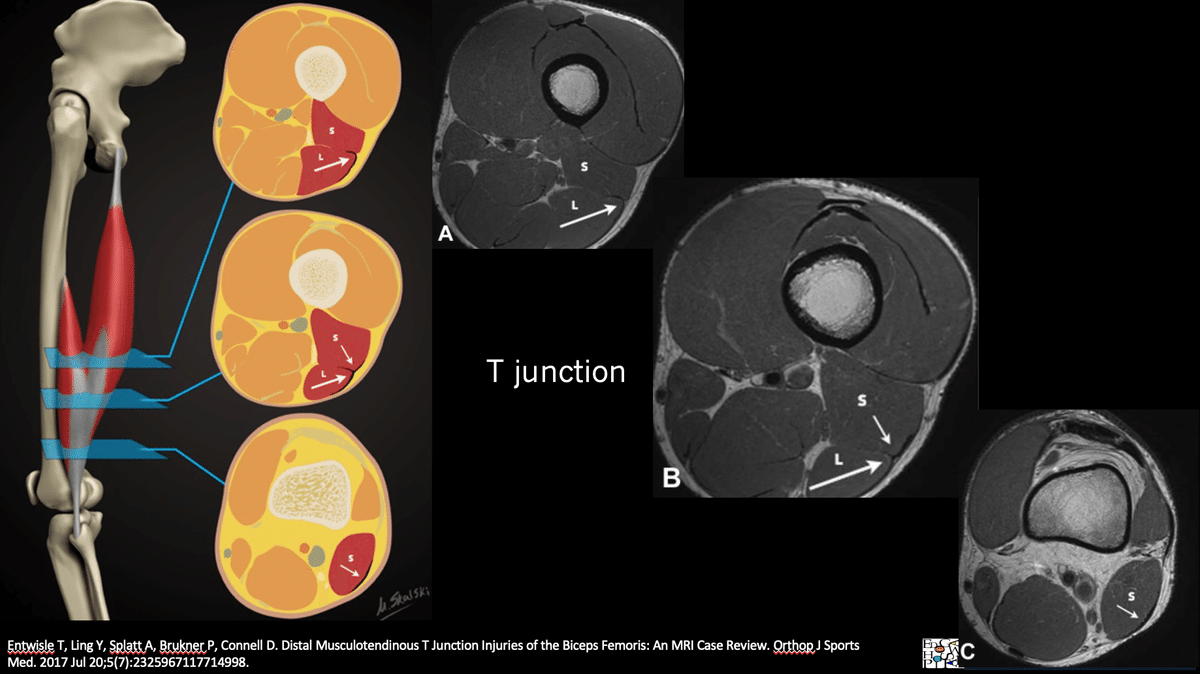

◉損傷後の修復が得られにくい大腿二頭筋遠位部損傷

(Distal Musculotendinous T Junction:DMTJ)

(Entwisle T, Ling Y, Splatt A, Brukner P, Connell D. Distal Musculotendinous T Junction Injuries of the Biceps Femoris: An MRI Case Review. Orthop J Sports Med. 2017 から引用)